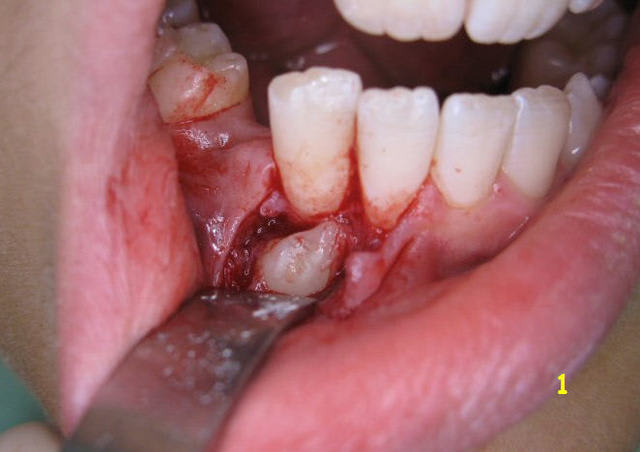

Ben... voici déjà la n°1 :

Sur l'OTP, le déplacement radiculaire de la 12 signe bien la position vestibulaire de 13, mais en bas...

Voici un cliché per-op.